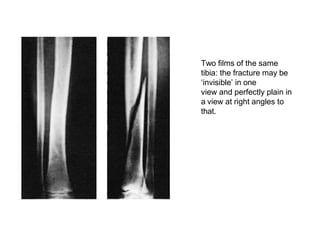

Two films of the same

tibia: the fracture may be

‘invisible’ in one

view and perfectly plain in

a view at right angles to

that.